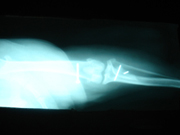

イリザロフ創外固定「下腿骨の粉砕骨折の整復」

交通事故により大腿骨(ももの骨)がバラバラにくだけてしまい、創外固定(特殊なピンで足の外から固定する方法)の手術をしました。治ったらピンはとります。